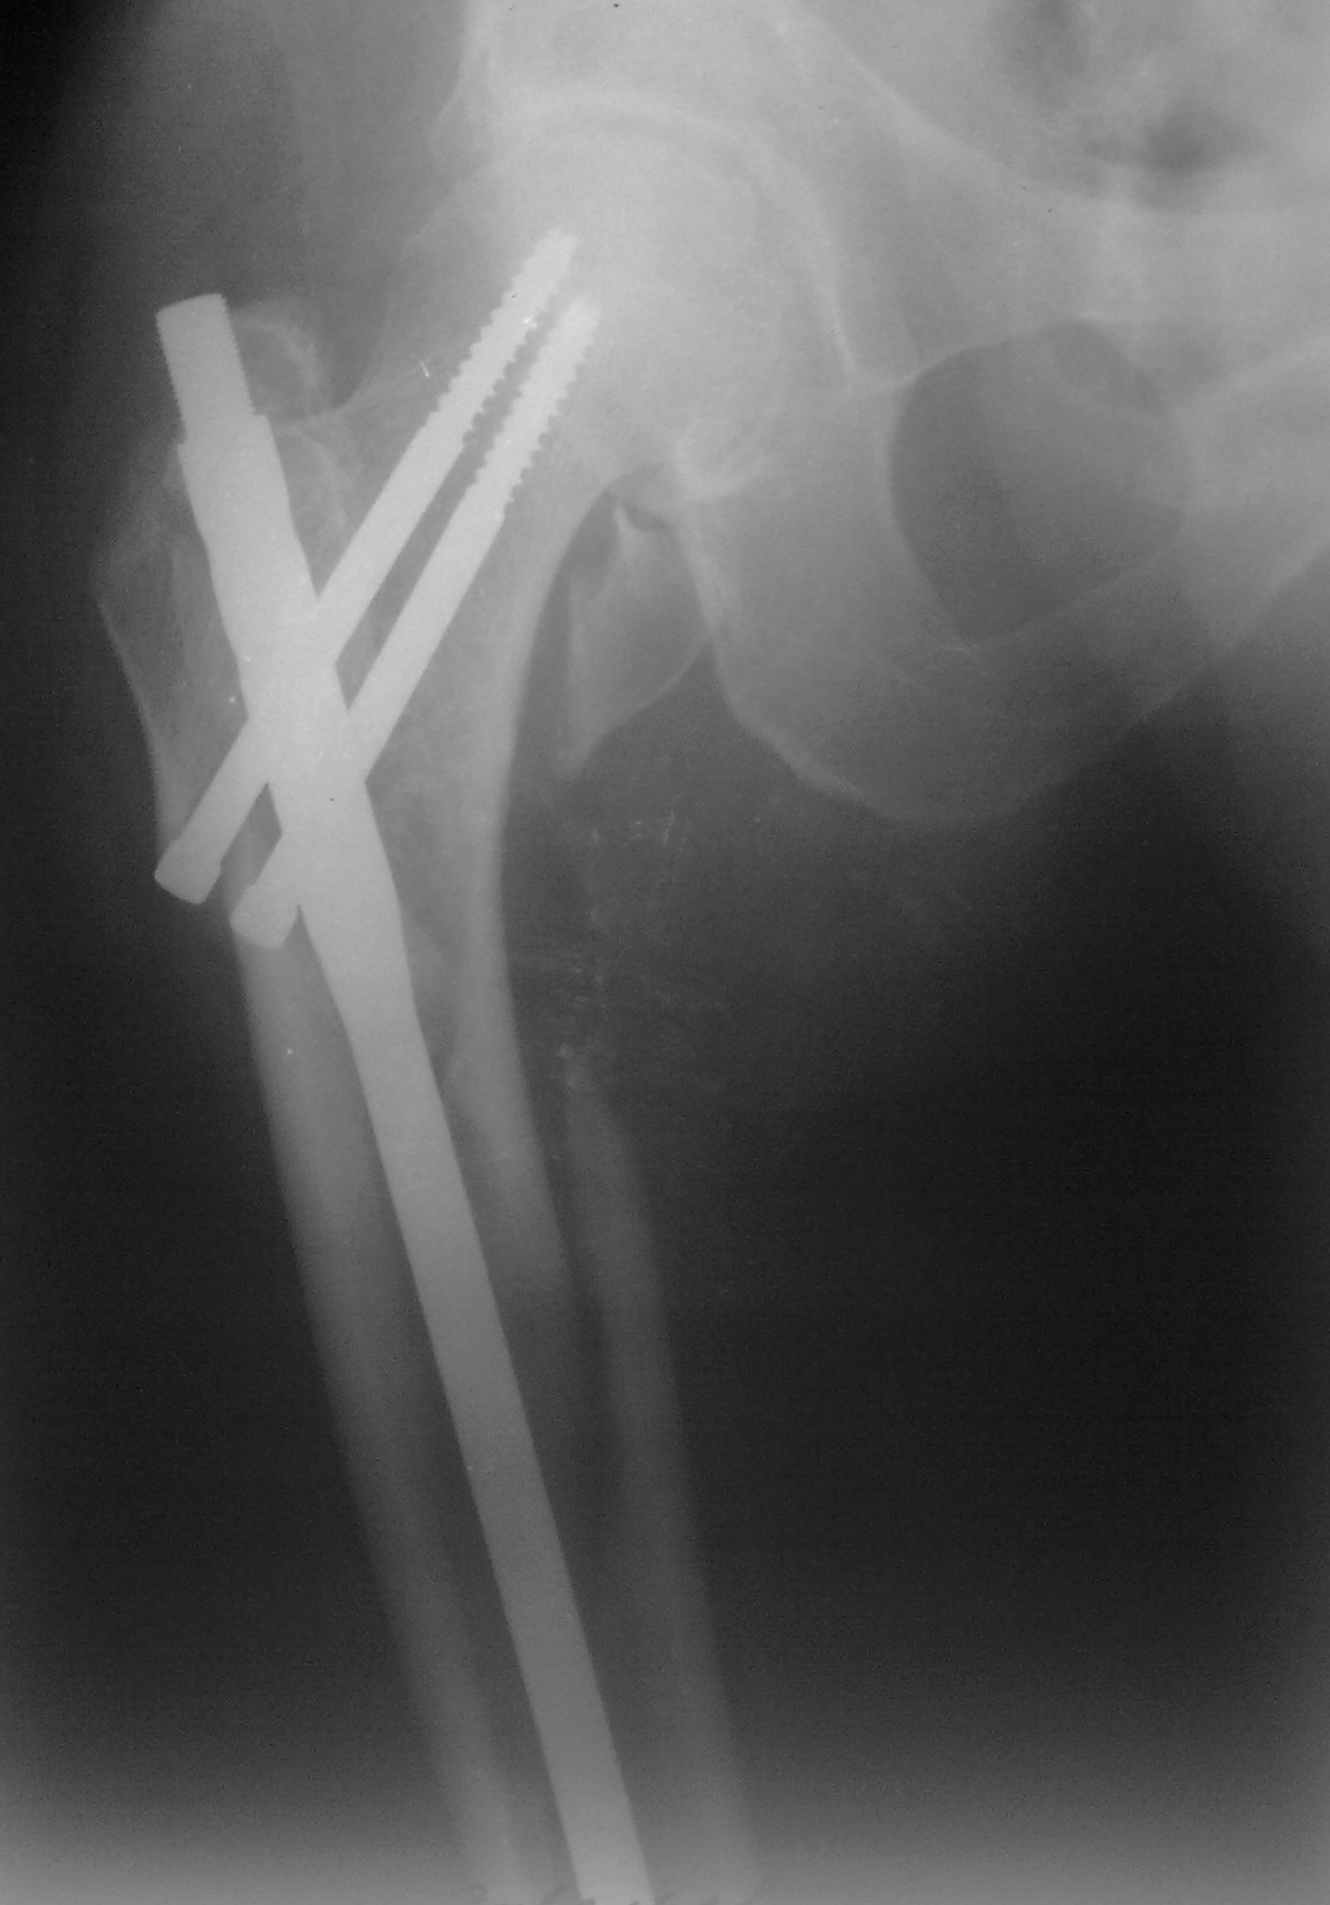

Пациент 83 года. Реконструктивный бедренный стержень Chm

Вложение не в текстовом формате было извлечено…

Имя     : 28092009070.jpg

Тип     : image/jpeg

Размер  : 64328 байтов

Url     : http://weborto.net:8080/pipermail/ortho/attachments/20101106/4466bdf3/attachment-0005.jpg